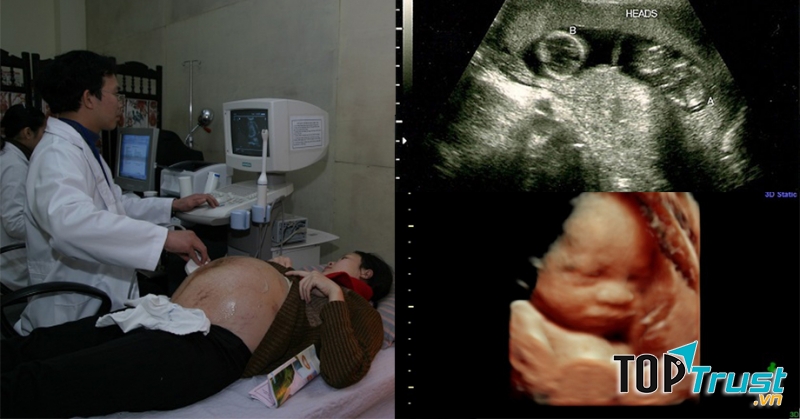

Phòng khám siêu âm sản khoa 187 Cát Dài là địa chỉ vô cùng quen thuộc được rất nhiều bà bầu lựa chọn. Đội ngũ bác sĩ thăm khám nhiệt tình, tỉ mỉ, kết hợp cùng máy móc siêu âm hiện đại, mang đến cho bạn sự thoải mái khi khám tại đây. Phòng khám hết sức sạch sẽ, được vệ sinh thường xuyên, nhờ vậy sản phụ có thể hoàn toàn yên tâm nhé.

Đi theo chủ trương khám bệnh an toàn, Phòng khám siêu âm sản khoa 187 Cát Dài thường xuyên cập nhật những phương tiện máy móc mới nhất, đảm bảo độ chính xác cao, tiết kiệm thời gian thăm khám và không khiến khách hàng cảm thấy mệt mỏi. Bên cạnh đó, phòng khám cam kết đưa ra mức giá hợp lý như đã niêm yết, đảm bảo trong khả năng chi trả của tất cả mọi người. Đây chính là điểm cộng được rất nhiều người đánh giá cao khi tới phòng khám.

- Siêu âm 4D thế hệ mới đặc biệt chuyển ảnh hoặc video clip thai nhi sang smart phone của quý khách

- Siêu âm chẩn đoán tổng quát; siêu âm 2D; 3D; 4D